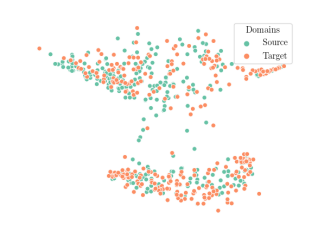

We compare the -distance of categorical features and domain features. Fig. 5 (a) shows that domain difference is higher in domain features than in categorical features. This indicates that domain features contain more domain information whereas categorical features are more domain-invariant. Fig. 6 shows the t-SNE plot of categorical features in both domains for MIDNet. From Fig. 6 (a), we observe that the categorical features learned by MIDNet enable the anatomical classification. Fig. 6 (b) shows that the learned categorical features are domain-invariant.

In addition, we utilize t-SNE plots for feature visualization in Fig. 10. Comparing Fig. 10 (a) and Fig. 10 (b), we observe that with mutual information disentanglement, (1) samples from the same category are more tightly clustered (see the top row) and (2) the source domain and the target domain are overlap more (see the bottom row). This indicates that mutual information disentanglement is important for learning categorical-focused and domain-invariant features. Fig. 10 (a), (c)-(d) show that the proposed method outperforms other state-of-the-art methods for learning category-discriminative and domain-invariant features, especially for unseen categories in the target domain (e.g., (a) vs. (d)).